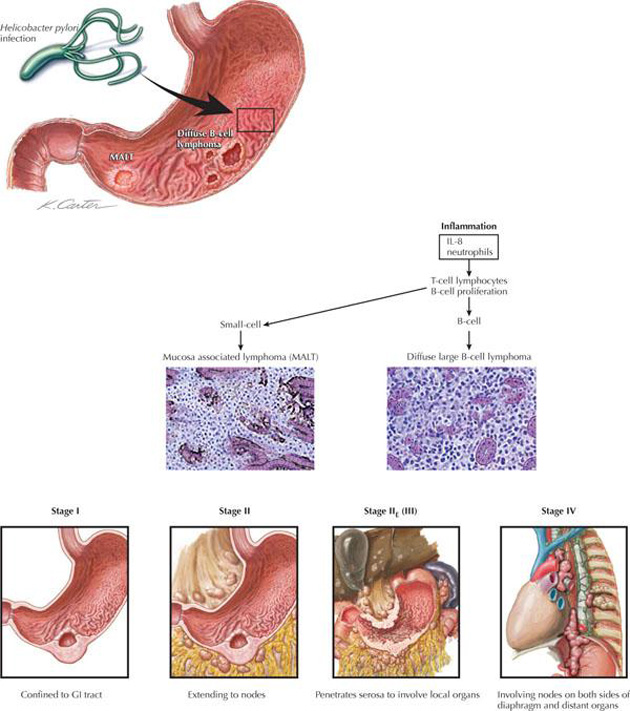

一 邊緣區B細胞淋巴瘤,黏膜相關淋巴組織型